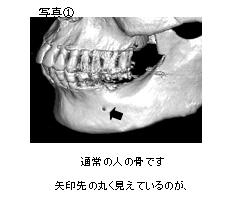

こちらは通常の人の顎の骨です(写真①)

通常の人の骨です。矢印先の丸く見えているのが下顎の中にある下歯槽神経の出口(オトガイ孔)です

下顎の中に丸い穴(矢印のところ)が見えると思います。

これは下歯槽神経といって下顎の中で一番大きな神経が骨の外にでてくる穴(オトガイ孔)です。

通常は写真①の方のようにちょうど骨の高さの真ん中ぐらいに位置します。